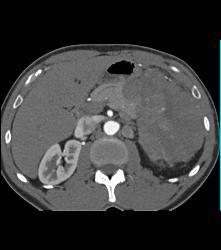

Antral Carcinoma